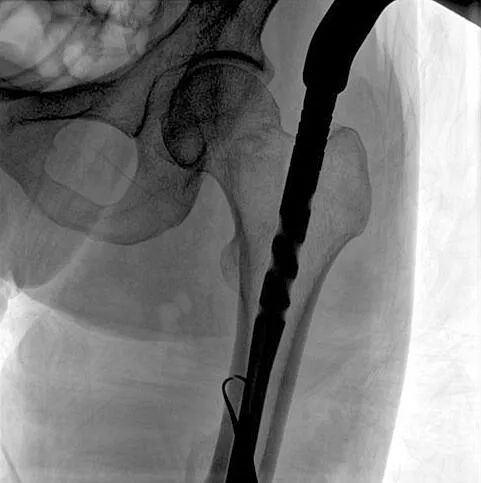

患者:男性,43岁,左股骨干骨折髓内钉内固定术

术中使用普爱医疗大平板一体式C形臂进行透视,判断骨折情况及克氏针、髓内钉等金属植入物的位置,进行调整。C形臂准确的术中定位,大大缩短了手术的时间,减轻了患者的痛苦,辅助手术顺利完成。

在进行髓内钉内固定术时,医生需要同时观察到入钉点和骨折部位的情况,普爱医疗大平板一体式C形臂采用30CM×30CM的平板探测器,能够呈现更广阔的成像面积,满足大部分长骨髓内钉内固定术的摄片需求。

术中定位准确、出血量少,术后影像显示股骨移位纠正,恢复良好力线,手术效果良好。